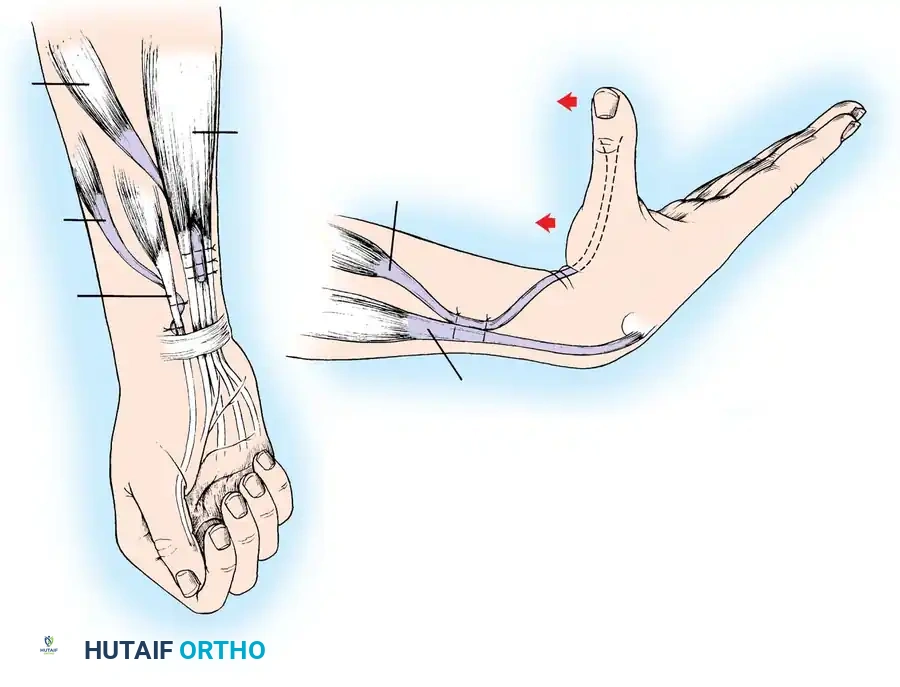

The posterior deltoid-to-triceps transfer, originally described by Moberg, is the gold standard procedure for establishing elbow extension. The posterior deltoid is synergistic with elbow extension and provides excellent excursion and power. Because the deltoid lacks sufficient length to reach the olecranon directly, the procedure requires an intercalated graft (fascia lata, toe extensors, or tibialis anterior tendon).

Lacey et al. reported excellent results using anterior tibial tendon grafts, noting that all patients achieved functional elbow extension and high satisfaction rates. Hentz et al. modified the procedure by utilizing fascia lata or directly attaching the deltoid to the mobilized triceps aponeurosis without a free graft, though this requires extensive mobilization.

Operative Technique: Posterior Deltoid-to-Triceps Transfer (Modified Moberg)

1. Make a 10- to 13-cm longitudinal incision along the posterior border of the deltoid muscle, extending distally toward the humeral insertion.

2. Raise thick fasciocutaneous flaps over the fascia of the deltoid to prevent skin necrosis. Identify the deltoid's humeral insertion.

3. Using a periosteal elevator and sharp dissection, elevate the posterior third to half of the deltoid tendon along with a robust strip of its periosteal insertion.

Surgical Pitfall: When splitting the deltoid muscle fibers in a distal-to-proximal direction, you must carefully palpate and visually inspect the deep surface of the muscle. The axillary nerve and posterior circumflex humeral vessels enter the muscle on its deep surface. Injury to the axillary nerve will denervate the transfer, resulting in catastrophic failure.

Graft Harvesting and Preparation:

1. Depending on surgeon preference, harvest an appropriate intercalated graft. Moberg originally utilized great toe extensors; however, the anterior tibial tendon or a robust strip of fascia lata is currently preferred due to superior tensile strength.

2. If using fascia lata, harvest a strip approximately 4 cm wide and 15 cm long. Tubularize the graft using a running locking non-absorbable suture.

Tendon Weaving and Fixation:

1. Weave the proximal end of the graft into the mobilized posterior deltoid muscle belly using a Pulvertaft weave technique. Secure it with multiple interrupted horizontal mattress sutures (e.g., 2-0 Ethibond or FiberWire).

2. Expose the distal triceps tendon and olecranon via a separate posterior longitudinal incision.

3. Create a longitudinal split in the triceps aponeurosis.

4. Pass the distal end of the graft subcutaneously from the proximal incision to the distal incision. Ensure the subcutaneous tunnel is wide enough to allow unhindered gliding of the graft.

Setting the Tension (The Critical Step):

1. The tension of the transfer dictates the functional outcome. The goal is to provide maximum extension power without permanently eliminating passive elbow flexion.

2. Adduct the arm and fully extend the elbow. Place the deltoid under maximal physiological tension.

3. Preliminarily suture the graft to the triceps aponeurosis or directly into an olecranon bone tunnel.

4. Test the passive range of motion. You must be able to passively flex the elbow to at least 90 degrees (some authors advocate for full passive flexion, though this risks a lax transfer). If the transfer is too tight, the patient will lose the ability to bring the hand to the mouth.

5. Once optimal tension is confirmed, permanently secure the graft. Place stainless steel surgical markers (clips) at measured distances proximal and distal to the repair site. This allows for radiographic verification of repair integrity postoperatively (Ejeskär technique).